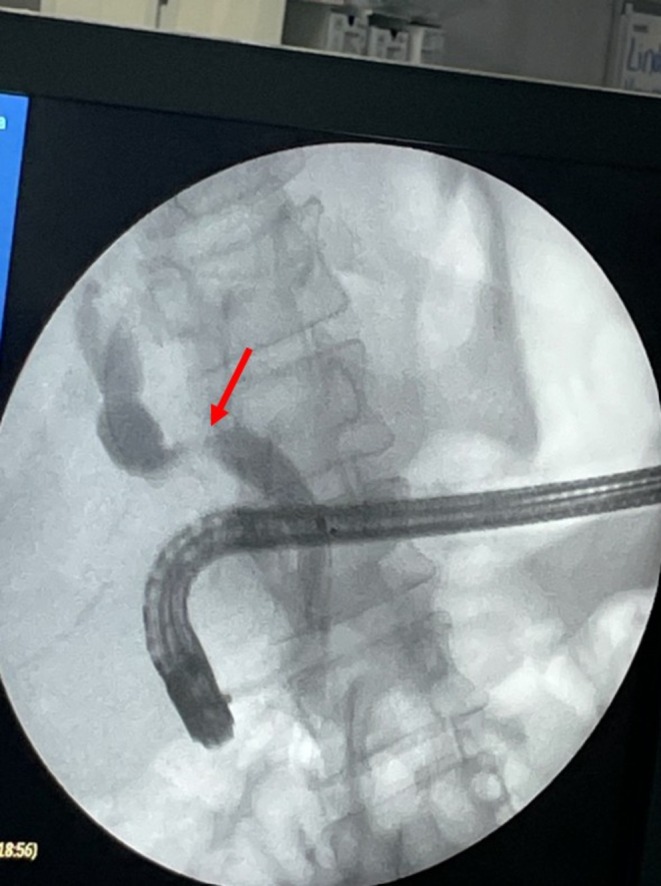

To proceed with TG‐ERCP, the roux limb and gastric remnant were both identified and dissected. The gastric remnant was mobilized, and an abdominal wall incision was made in the upper left quadrant above the left extension of the Mercedes incision. A gastrotomy was made, and a 15 mm trocar was placed through it into the gastric lumen, as previously described (Figure 2) [ref. 14]. The anterior wall of the remnant was then stammed to the abdominal wall with a 3–0 barbed suture. The abdominal cavity was temporarily closed, and overlying drapes were placed, allowing access solely to the 15 mm trocar (Figure 3). The advanced endoscopist then cannulated the trocar with the side‐viewing endoscope, and an ERCP was performed in the usual fashion (Figure 4). A single biliary stricture was identified at the anastomosis, and a 10 cm, 7‐French plastic stent was placed across (Figure 5). No balloon dilation of the anastomosis was performed due to the recentness of the anastomosis. The trocar and the overlying drapes were removed, and a 24‐French gastrostomy tube (G‐tube) was placed through the gastrotomy for future biliary access and enteral nutrition, if deemed necessary. Liver biopsy was performed that demonstrated marked canalicular cholestasis and bile ductular proliferation consistent with the biliary obstruction. There was no evidence of rejection.

In this case presentation, the use of TG‐ERCP for management of a postoperative biliary stricture was successful as evidenced by down trending post‐procedural bilirubin and liver function enzymes and resolution of the CBD dilation. There were no postoperative complications, and the patient was discharged to inpatient rehabilitation after 7 days. The procedure not only treated the stricture but also allowed for enteral tube placement through the gastrotomy. This strategy gives the endoscopist access outside of the operating room for easy stent removal and/or future, more advanced management if the initial plastic stent fails, such as long‐term intubation with a removable metal stent.